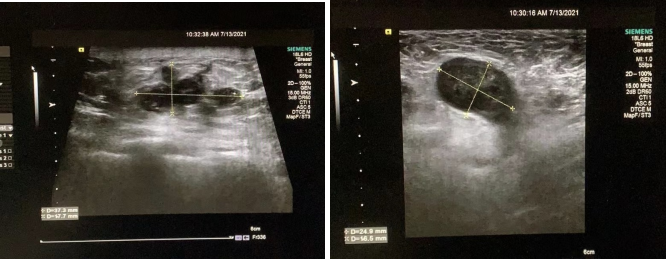

乳腺彩超示(2021-07-13,图1):右乳房7:00距离乳头约3cm,距离皮肤约1.4cm探及低回声团块,大小约3.7*1.8*1.8cm,形态不规则,内示多枚强回声,纵横比<1,内示血流信号,超声弹性成像质地偏硬(4分)。右侧腋窝多发低回声结节,最大约2.5*1.7cm,内示血流信号。

图1.乳腺彩超示图

乳腺彩超示(2021-08-27):右乳房7:00距离乳头约4.8cm,距离皮肤约0.9cm探及低回声团块,大小约1.7*1.0*1.3cm,形态不规则,内示多枚强回声,纵横比<1,内血流信号不明显,超声弹性成像质地偏硬(4分)。右侧腋窝多发低回声结节,最大约2.4*1.5cm,内示血流信号。提示右乳肿瘤缩小明显,治疗方案疗效确切,疗效评估PR。继续按既定方案执行6周期化疗。

彩超示(2021-12-15):右乳房7:00距离乳头约5.2cm,距离皮肤约1.4cm探及低回声团块,大小约0.5*0.7*0.5cm,形态不规则,边界不清晰,纵横比<1,血流信号不明显。右侧腋窝探及淋巴结声像,淋巴门存在,皮髓质分界清,大小约1.1*0.6cm,皮质稍厚。

图5.2021-07-20彩超图(上)vs2021-12-15彩超图(下)